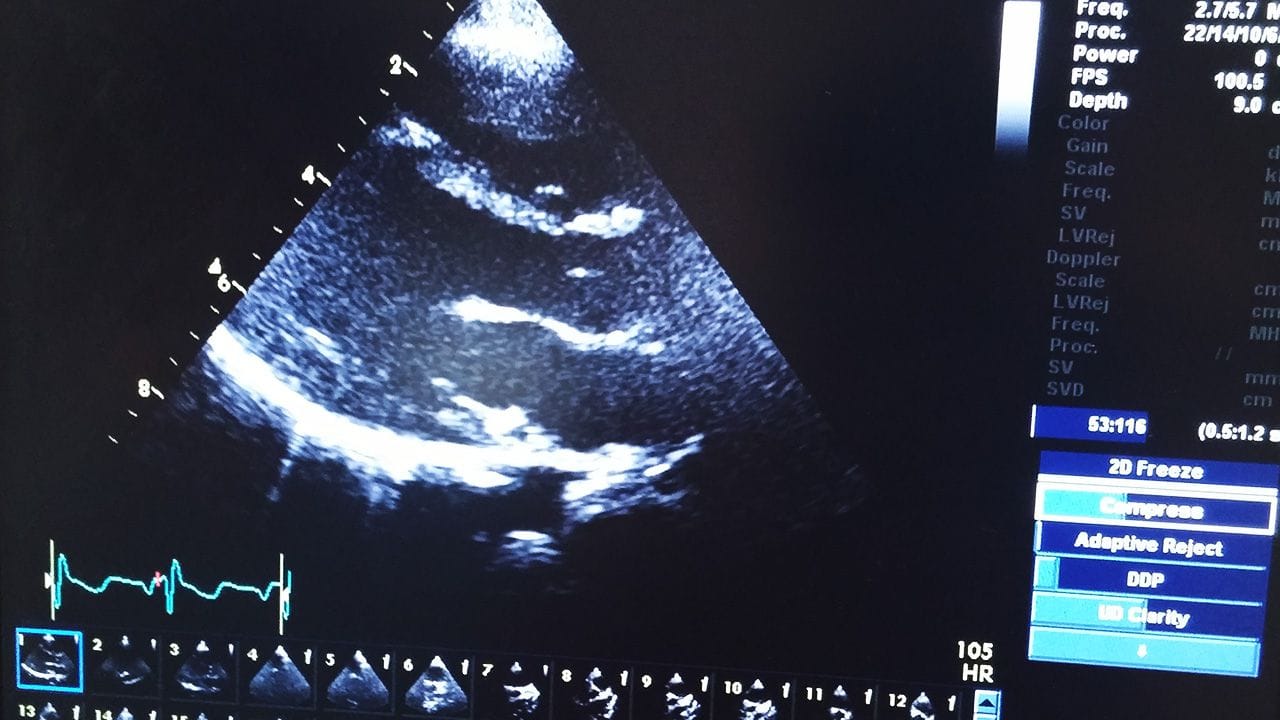

Lucien and I took another road trip up to London, to have follow up on his Kawasaki disease and there were no signs on any lesions on his heart so he was declared healthy and the doctors don’t feel a need to follow him any more.

Lucien Eriksson and his echocardiogram.

His heart.